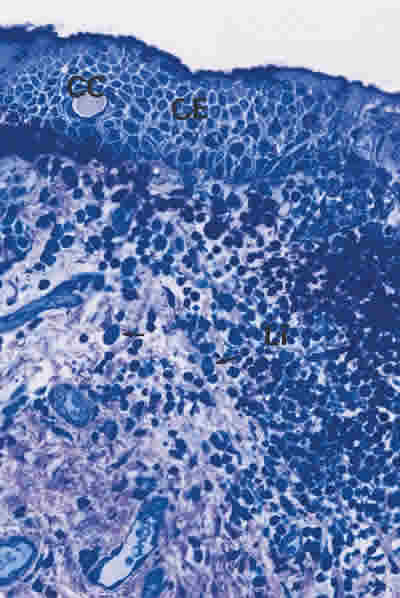

Figura 13

BIOPSIA EN UN PACIENTE CON SS1-GRADO III. LA CONJUNTIVA NO SUELE PRESENTAR CÉLULAS CALICIFORMES, CUANDO LO HACEN ESTÁN GENERALMENTE ALTERADAS (CC). LAS CÈLULAS EPITELIALES (CE) ESTÁN MUY ALTERADAS Y SEPARADAS. EL TEJIDO CONECTIVO ES MUY DENSO, CON NUMEROSOS LINFOCITOS (Li) AGRUPADOS EN FOCOS Y ESCASO NÚMERO DE CÈLULAS PLASMÁTICAS (FLECHA ARRIBA). TINCIÓN AZULES DE RICHARDSON. MAGNIFICACIÓN ORIGINAL X40.